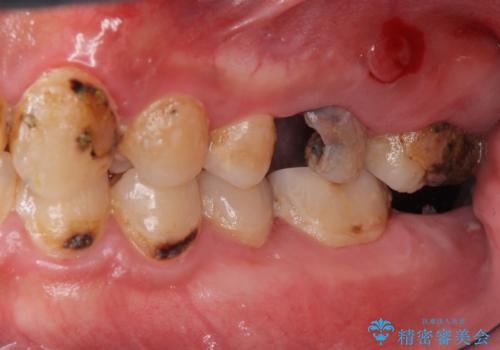

- 口の中をマスク生活の間に全て治したい、見た目を良くしたいとの事で来院。

まず徹底的に虫歯を取り除き、保存が出来ない部位は抜歯(親知らずを含む)を行い、根管治療が必要な部位は精密根管治療を行いました。

その後、インプラント治療、セラミック治療を行いました。

一度治療するはを全て仮歯に変えて、歯茎を整えてからセラミックを装着しました。

また、虫歯が歯肉の中まである場合はAPF(歯肉弁根尖側移動術)も行なっています。